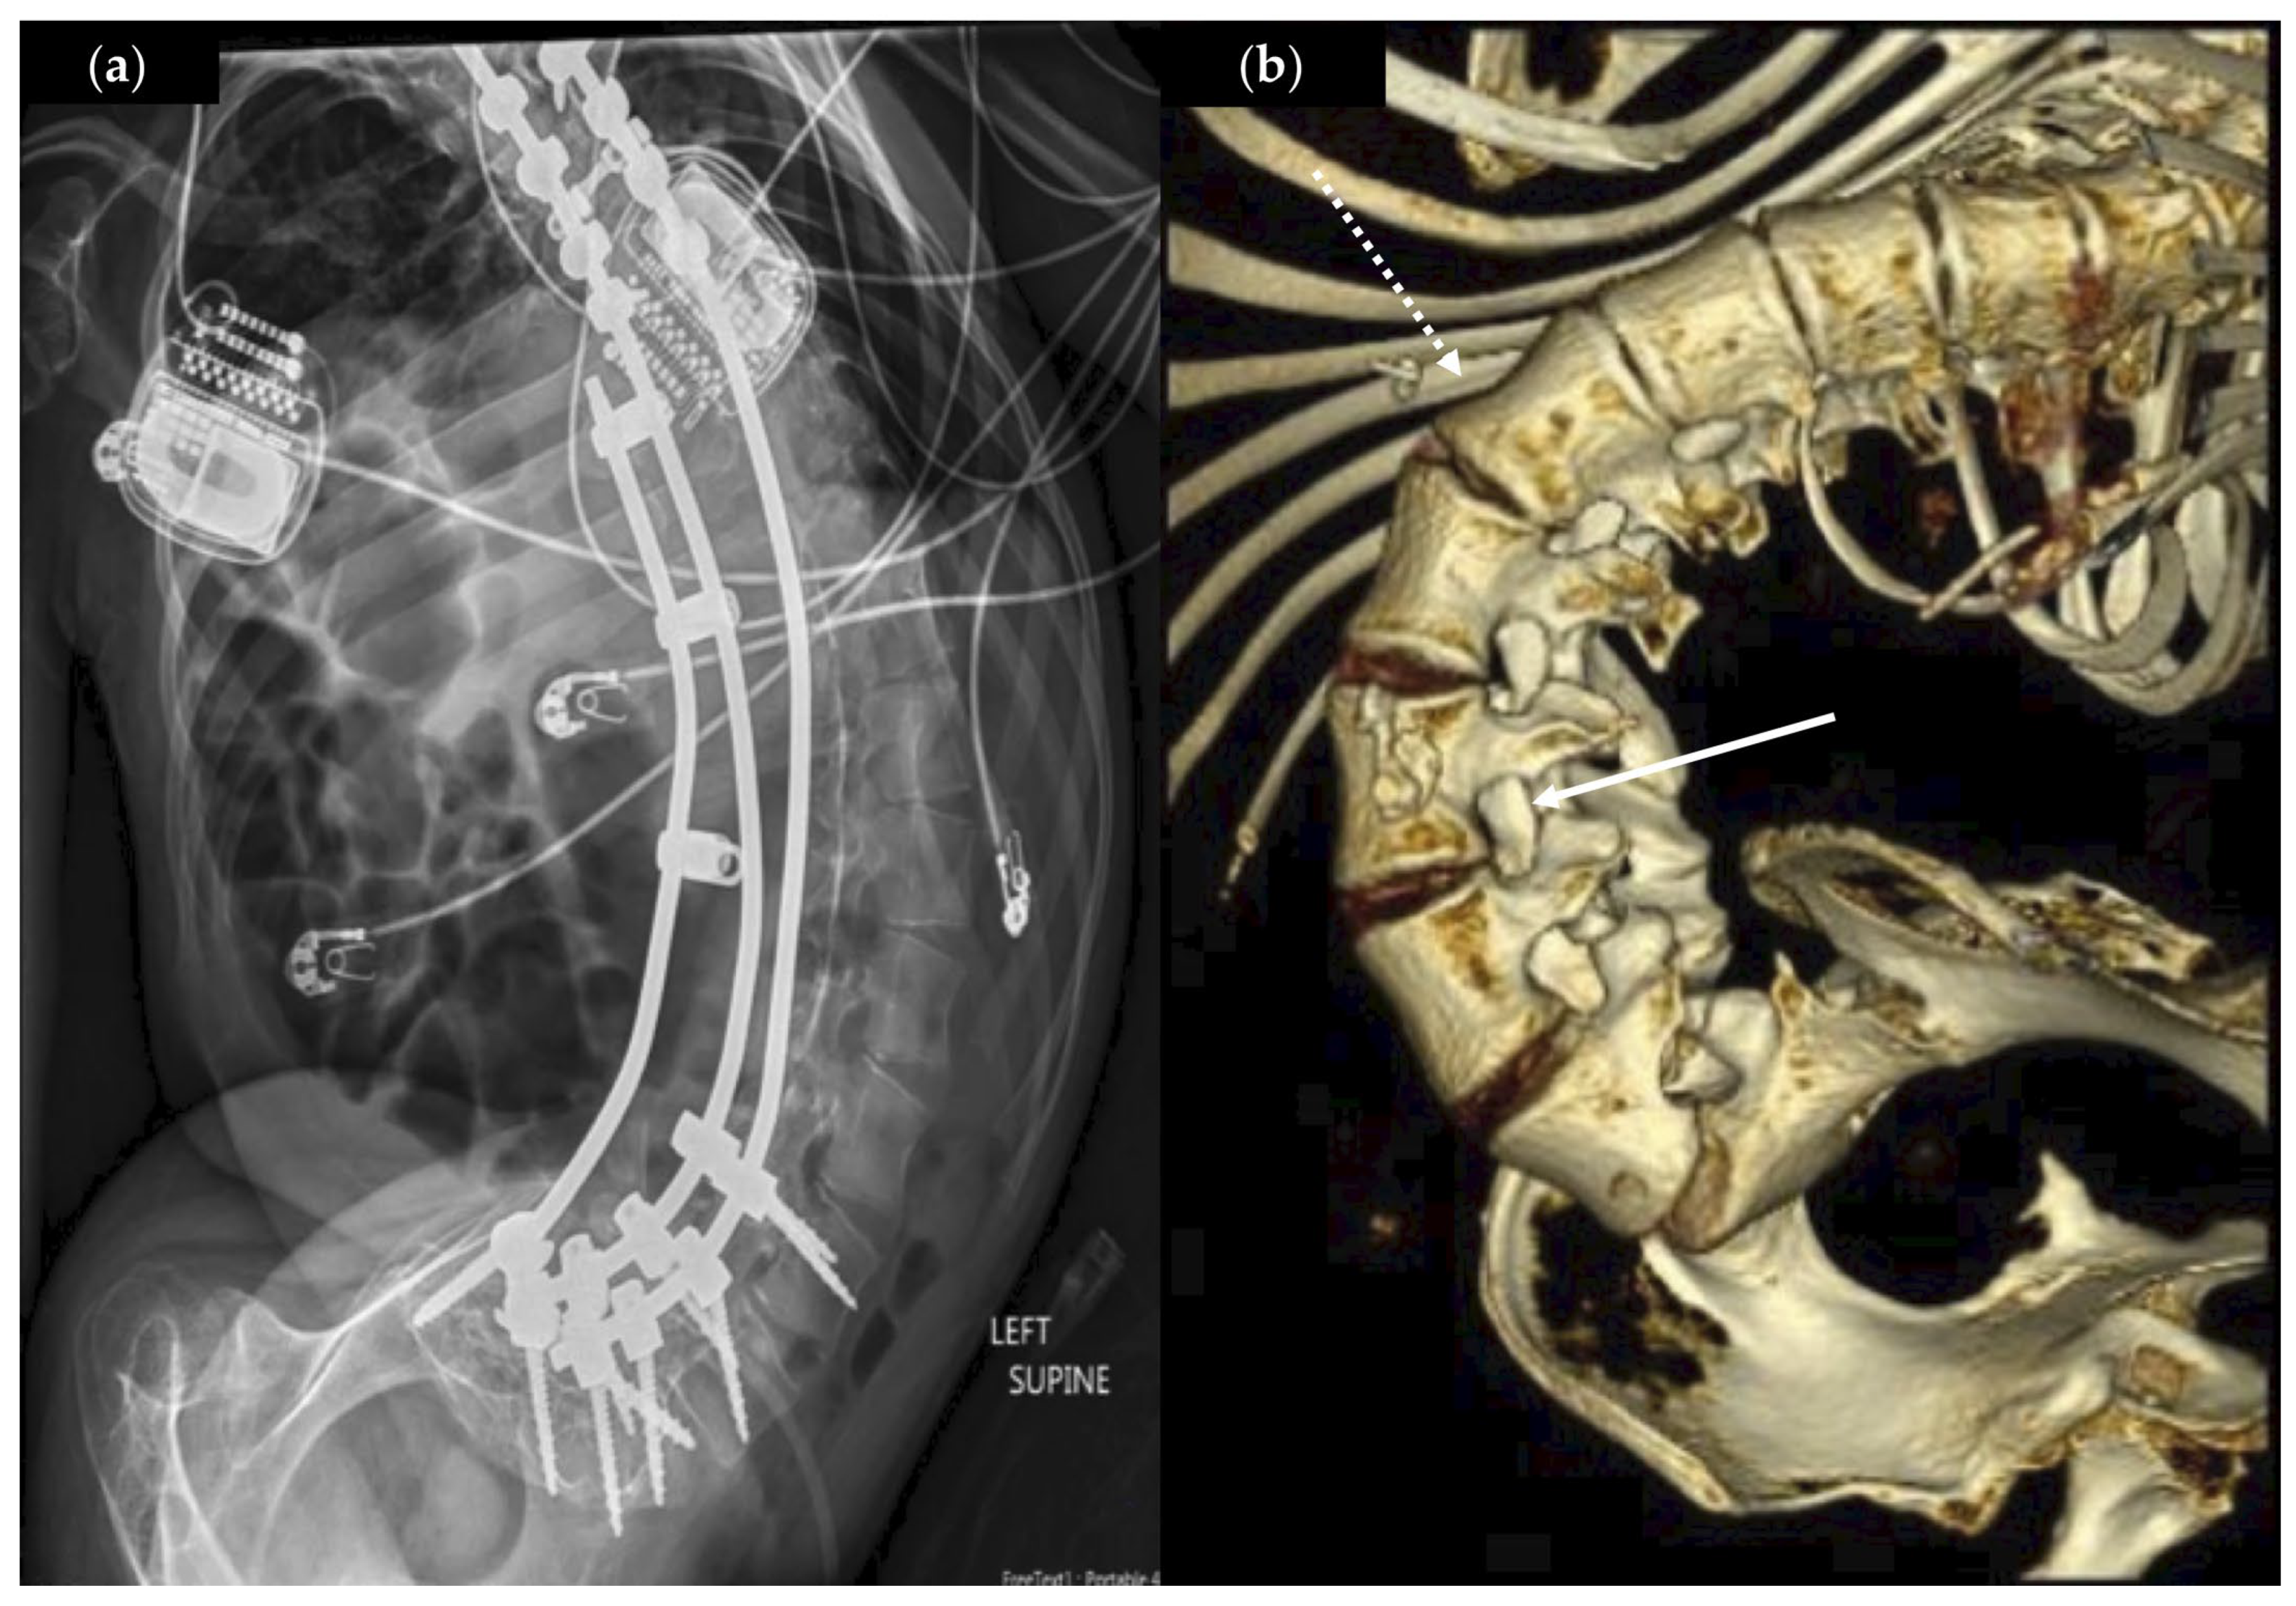

| 1 | 22, M | Asian | Quadriplegia, mixed | CP (HIE) | V | Y | Y | 19.9 | T10-L4, 51.5 L | +2, L3 | Y | Y, bolus ITB test dose |

| 2 | 21, M | Hispanic | Quadriplegia, spastic | CP (unknown) | V | N | Y | 19.3 | T7-L4, 64 D | +4, L3 | Y | N |

| 3 | 21, F | Hispanic | Quadriplegia, spastic | SMA2 | V | Y * | Y | 14.8 | T12-S1, 143 D ^ | +4, T12 | N | N |

| 4 | 18, M | Hispanic | Quadriplegia, mixed | CP (pre-term) | V | N | Y | 19.1 | T9-L5, 82 L | +4, T12 | Y | Y, DBS |